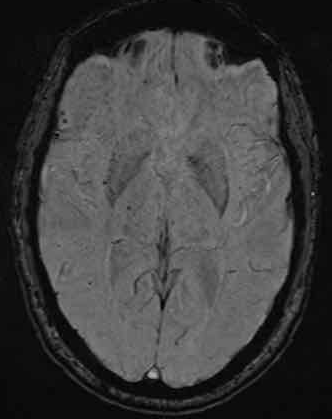

下图 一位46岁的男子骑摩托车时受伤。

瞳孔无反应性,瞳孔扩张。

CT:额叶点状出血。

继续做核磁共振成像

弥漫性轴索损伤(DAI)MRI表现

- 累及皮质下区、胼胝体、右侧丘脑和壳核、脑干、小脑脚和右侧小脑半球。

- 轻度全球萎缩。

MRI可准确诊断DAI,包括T2*GRE或SWI。

DAI在颅脑损伤患者MRI上的存在,更有可能导致不良的功能结局。